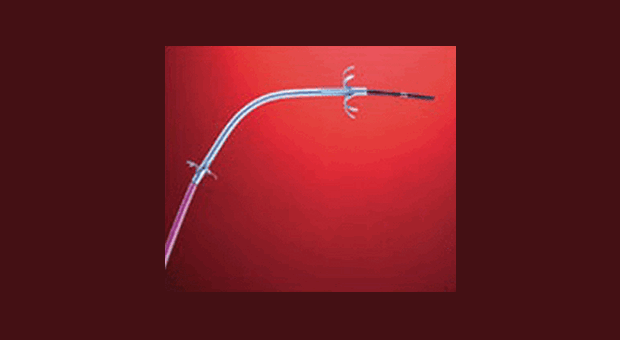

Стентирование холедоха с целью паллиативного лечения рака поджелудочной железы (ликвидации механической желтухи) первым применили Soehendra and Reynders-Frederix в 1979 году [11]. Не очень сложная техника выполнения данной манипуляции и ее низкая травматичность весьма привлекательны. Основным недостатком данного метода является высокая вероятность обтурации протеза через 3-6 месяцев после постановки в результате отложения на нем солей желчных кислот и бактериальных пленок [8]. Теоретические обоснованные попытки предотвратить это осложнение путем назначения препаратов урсодезоксихолевой кислоты и антибиотиков не показали свою эффективность в контролируемых исследованиях. Относительно недавно опубликован анализ 5 работ (включавших 258 пациентов) посвященных данной проблеме продемонстрировавший, что ни антибиотикотерапия ни комбинация антибиотиков с урсодезоксихоливой кислотой не приводила к значимому увеличению длительности проходимости стента или удлинению продолжительности жизни пациента [5]. В результате исследования выполненного французскими ученными даже был сделан вывод том, что урсодезоксихолевая кислота может способствовать обструкции стента [4]. Была предпринята попытка разработки новых стентов с антибактериальным (например серебряным) покрытием. Металлические само-расправляющиеся стенты сохраняют проходимость дольше, чем пластиковые, около 6 и 3 месяцев соответственно [3, 12]. Однако их стоимость гораздо выше, $1000-1500 и $ 33 соответственно. Кроме того, использование металлических стентов ассоциируется с риском прорастания в них опухоли, что вызывает весьма сложную для последующей ликвидации обструкцию. Пластиковый и металлический стенты представлены на рис. 1-2.